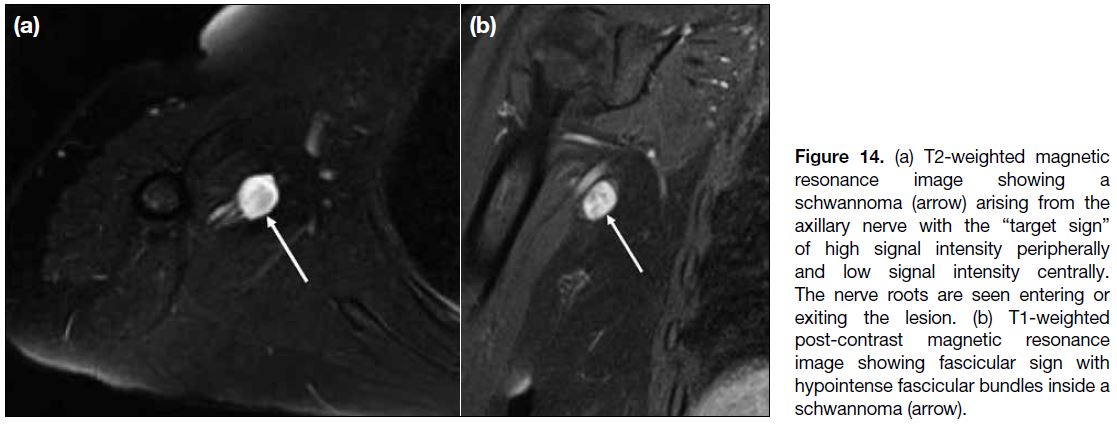

Peripheral nerve sheath tumours are divided into two

benign entities, neurofibroma and schwannoma, and

a malignant form, malignant peripheral nerve sheath

tumour.[15] MRI plays an important role in the identification

and characterisation of these tumours. They commonly

appear as fusiform lesions and demonstrate low to

intermediate signal intensity on T1-weighted sequence

and high signal intensity on T2-weighted sequence.[15]

Some other suggestive imaging features include the

“entering or exiting nerve sign”, the “split-fat” sign,

the “target sign” (Figure 14a), the “fascicular sign”

(Figure 14b), and atrophy of the muscles supplied by the

involved nerve.[15]

Figure 14. (a) T2-weighted magnetic resonance image showing a schwannoma (arrow) arising from the axillary nerve with the “target sign” of high signal intensity peripherally and low signal intensity centrally. The nerve roots are seen entering or exiting the lesion. (b) T1-weighted post-contrast magnetic resonance image showing fascicular sign with hypointense fascicular bundles inside a schwannoma (arrow).